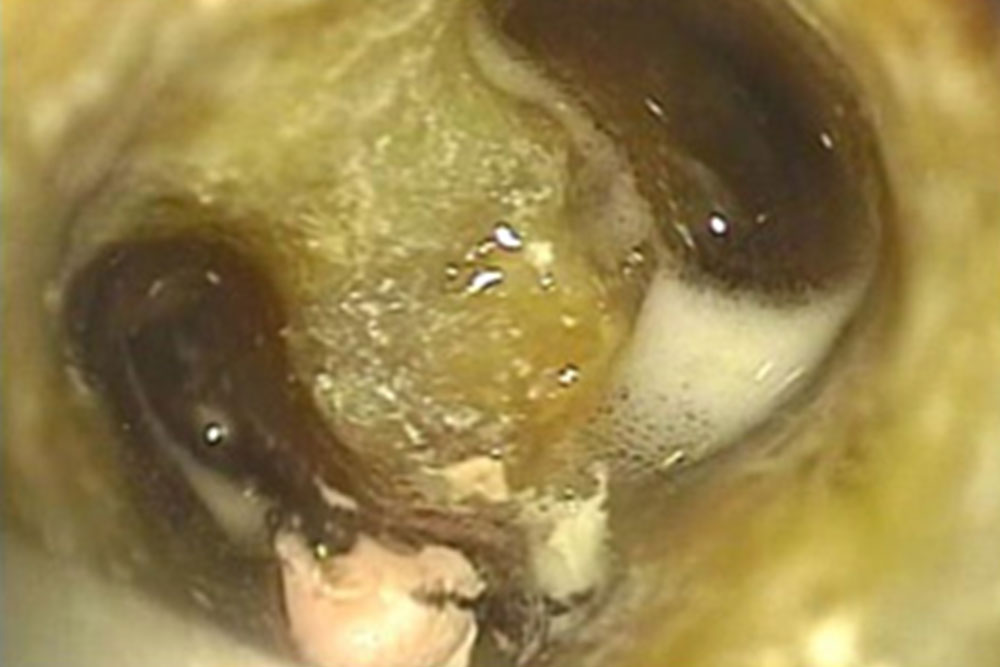

マイクロスコープ

歯科顕微鏡とも呼ばれ、視野を30倍まで拡大する事が可能な精密機器です。拡大する事で細部に対して、精度の高い処置が行えるようになります。

歯科顕微鏡とも呼ばれ、視野を30倍まで拡大する事が可能な精密機器です。拡大する事で細部に対して、精度の高い処置が行えるようになります。

当院では、根管治療や歯周病をはじめ、様々な治療に用いて精密な処置を行っています。

条件が揃えば、通常抜歯となる歯でも保存することが可能です

肉眼の約10倍拡大図下での治療図

肉眼の約20倍拡大図下での治療図

肉眼の約30倍拡大図下での治療図